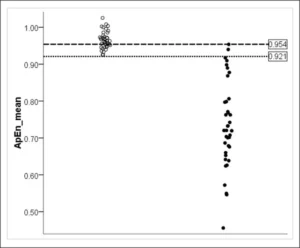

Leggi di Più..Isolamento Funzionale all’Interno della Corteccia

Lo studio utilizza l’analisi non lineare dell’EEG per valutare la...